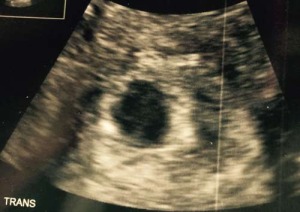

Ultrasound confirmed uterine placement and

we have ruled out ectopic.